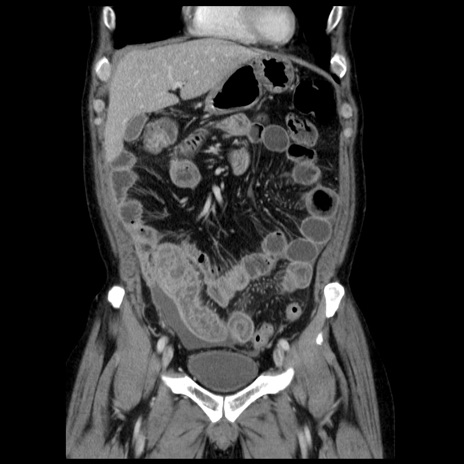

症例29(冠状断像)

【症例】40歳代男性

【現病歴】2日前から胃痛あり。徐々に周期的な激痛に変化した。本日になっても激痛があるため受診。

【身体所見】意識清明、BT 38-39℃台あり、腹部:膨満、やや硬、右下腹部に圧痛あり。

【データ】WBC 8500、CRP 23.26